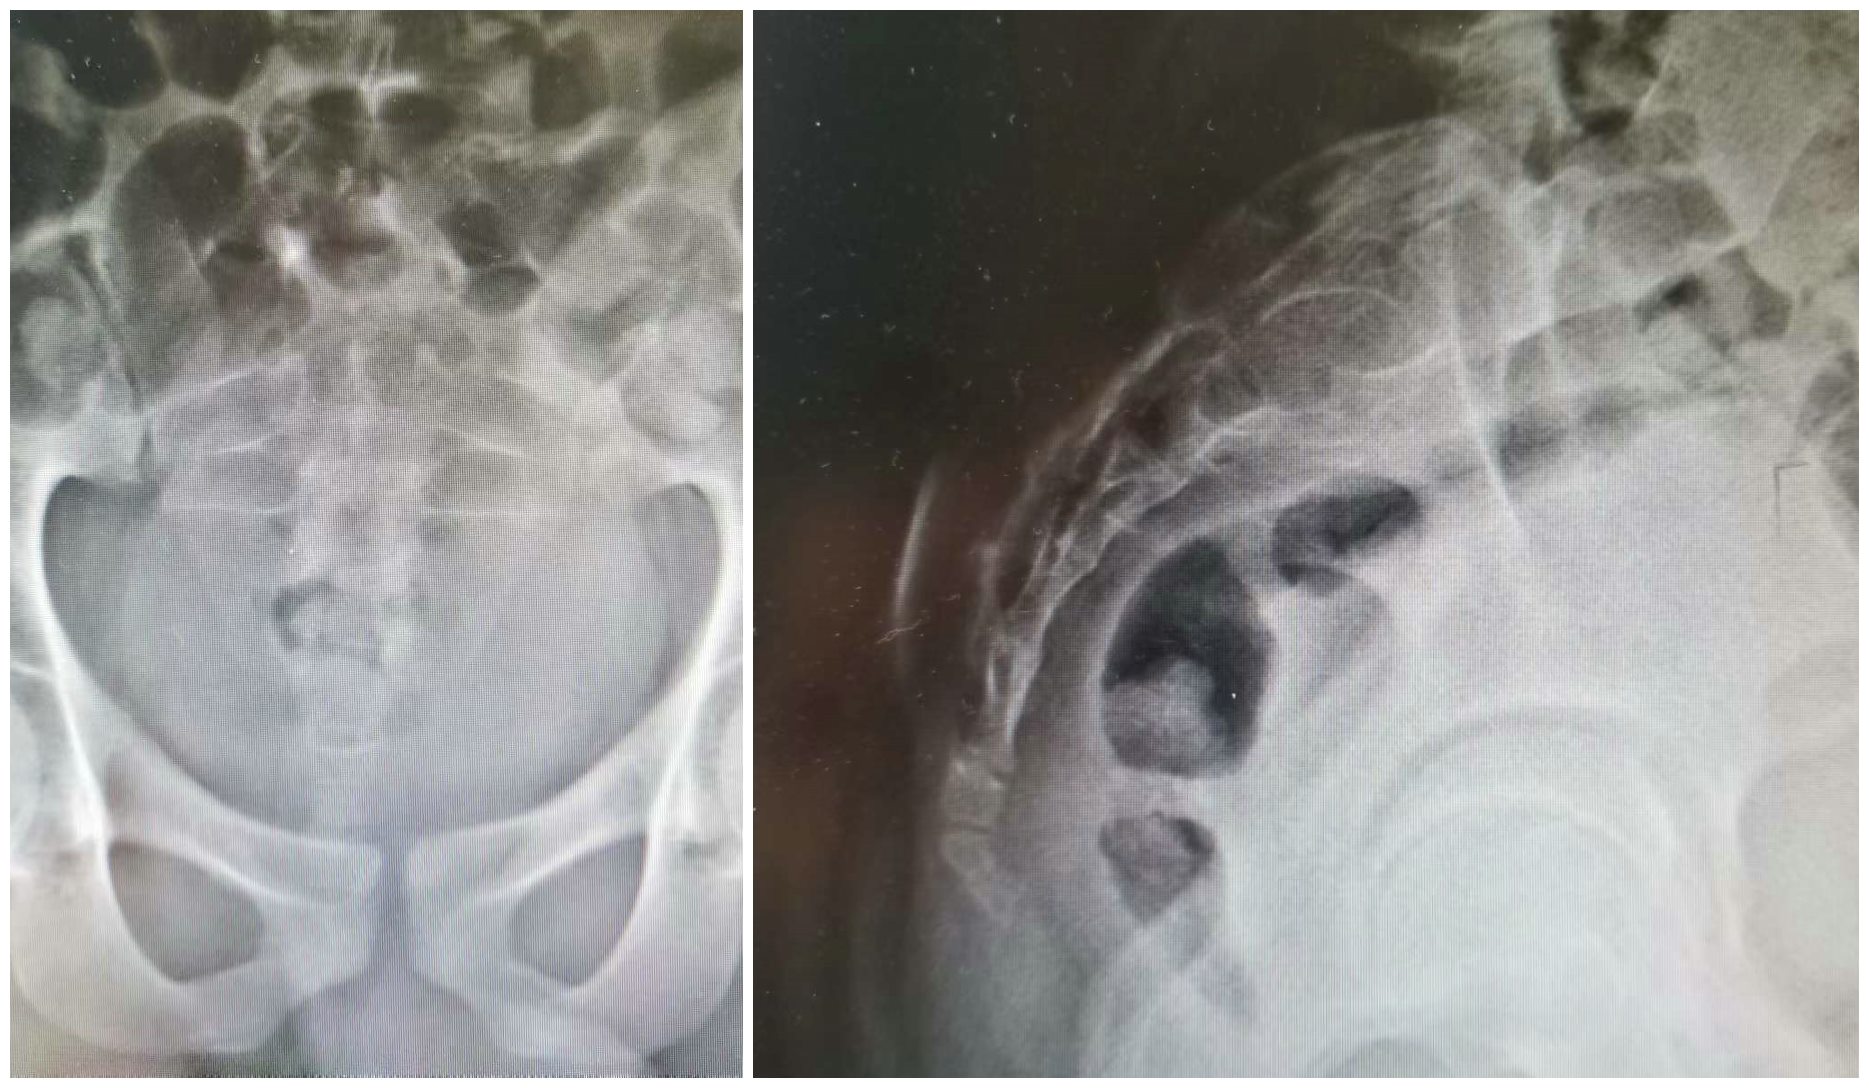

患者为18岁男性,因渐进性加重的骶部疼痛伴下肢无力半年收住入院(图片1、2)。入院后,完善相关检查,穿刺活检诊断为骶骨2、3巨细胞瘤,ki67达到60%,属于Campanacci3级(图片3)。影像显示瘤体侵袭骶骨2、3椎体,突破骶骨前方,向后突入椎管,压迫骶神经(图片1、2)。

图2 术前CT